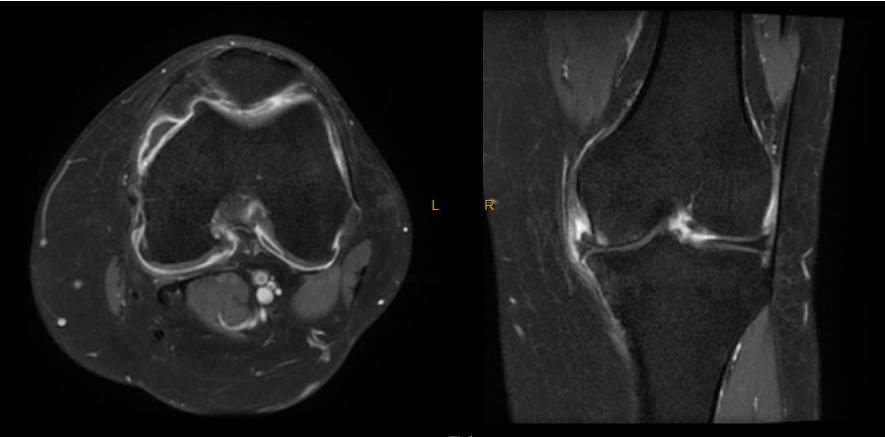

MRI angiography shows the genicular arteries supplying the knee and associated hypervascularity on the medial side. This hypervascularity is caused by neo-vessels as a result of inflammation, with further neo-nerves growing in and causing pain.

MRI knee with a post gadolinium T1FS sequence showing marked enhancement of the knee joint affecting the synovium with a small effusion. The hypervascularity demonstrated here is associated with neo-nerve growth, resulting in severe pain.

MR angiography showing the genicular arteries of the knee.

MRI demonstrates marked synovial hyperenhancement in a patient with knee osteoarthritis. A great target for TAME.